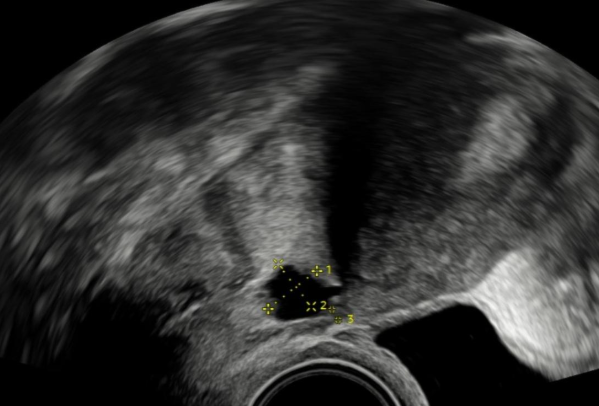

Děložní niche je defekt na děložní stěně, který vzniká po císařském řezu. Může způsobovat chronické špinění po menstruaci, bolesti v podbřišku a v některých případech i neplodnost. Tento stav často zůstává nediagnostikovaný, protože příznaky mohou být nespecifické a ženy si je nespojují s předchozím porodem. Na ultrazvuku nebo hysteroskopicky však niche dokážeme jasně identifikovat.

Děložní niche